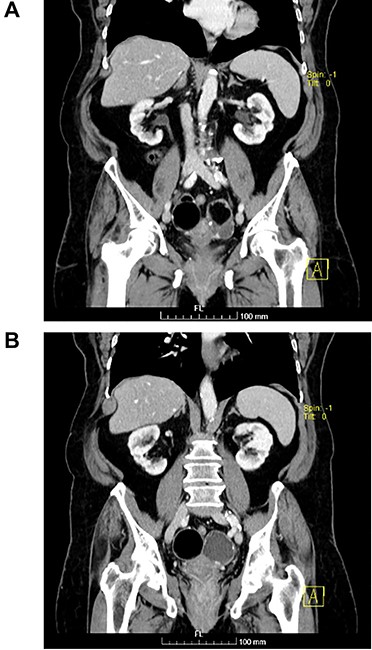

(A and B) Sagittal images of CT showing bilateral ovarian lesions.

The authors report the case of an asymptomatic 76-year-old female patient, referred to our Gynaecologic Clinic, due to suspicious adnexal lesions on a pelvic ultrasound (US). Menopause occurred at age 53. She had no history of abnormal uterine haemorrhage. Her menstrual cycles had been regular. She had had three gestations: two late abortions and one normal delivery, after which she breastfed. At our clinic, upon examination, vulva, vagina and cervix had no apparent lesions. The vaginal US revealed a right adnexal avascular cystic lesion of 65 mm, a left adnexal hyperechogenic cystic lesion of 60 mm, a normal sized uterus, a diffusely heterogeneous myometrium, an endometrial thickness of 8 mm and heterogenous intracavitary liquid. Her risk of ovarian malignancy assessment (ROMA) score was 28.1%, for a cut-off of 25.3%. Cancer antigen (CA) 125 and Human epididymis protein 4 (HE4) were 25.9 and 98.2, respectively. Lactate dehydrogenase (LDH), alpha fetoprotein (AFP) and beta human chorionic gonadotropin (bHCG) were normal. She subsequently had a magnetic resonance (MR) done (Fig. 1), which suggested bilateral ovarian teratoma. She also had an upper digestive endoscopy and a hysteroscopy that were normal and a computed tomography (CT) done (Figs 2–4) that showed: in the right adnexal region, a solid well-demarcated tumoural mass of 55 mm, with predominantly fat density, peripherical calcifications and a central hyperdense image (similar to a tooth), suggestive of a teratoma; in the left adnexal region, a predominantly cystic bilobated tumoural mass of 65 mm, with peripherical calcifications and an area of fat density, also suggestive of teratoma; and no additional disease. This case was presented at our Multidisciplinary Tumour Board, where surgery was proposed. Thus, she underwent exploratory laparotomy, peritoneal washing, total hysterectomy and bilateral adnexectomy, which ran uneventfully. Intra-operative frozen section excluded ovarian malignancy. She had an uneventful recovery and was discharged home on the third post-operative day. The pathological report revealed bilateral mature cystic teratoma with representation of the three germinative layers and thyroid parenchymal tissue (struma ovarii) (Fig. 5). Both ovaries were atrophic and had a cavitated lesion covered by respiratory epithelium with hyaline cartilaginous, adipose, smooth muscular and mucosa-associated lymphoid tissues (positivity for CD3 and CD20), seromucinous glands and thyroid follicles (homogenous positivity for thyroglobulin). Thyroid follicles were well differentiated, without features of malignancy. Fallopian tubes were normal. There were also uterine leiomyomas and a mucosal endocervical polyp. She was euthyroid and had a thyroid US done, which was normal. Follow-up at first post-operative month, remaining asymptomatic.